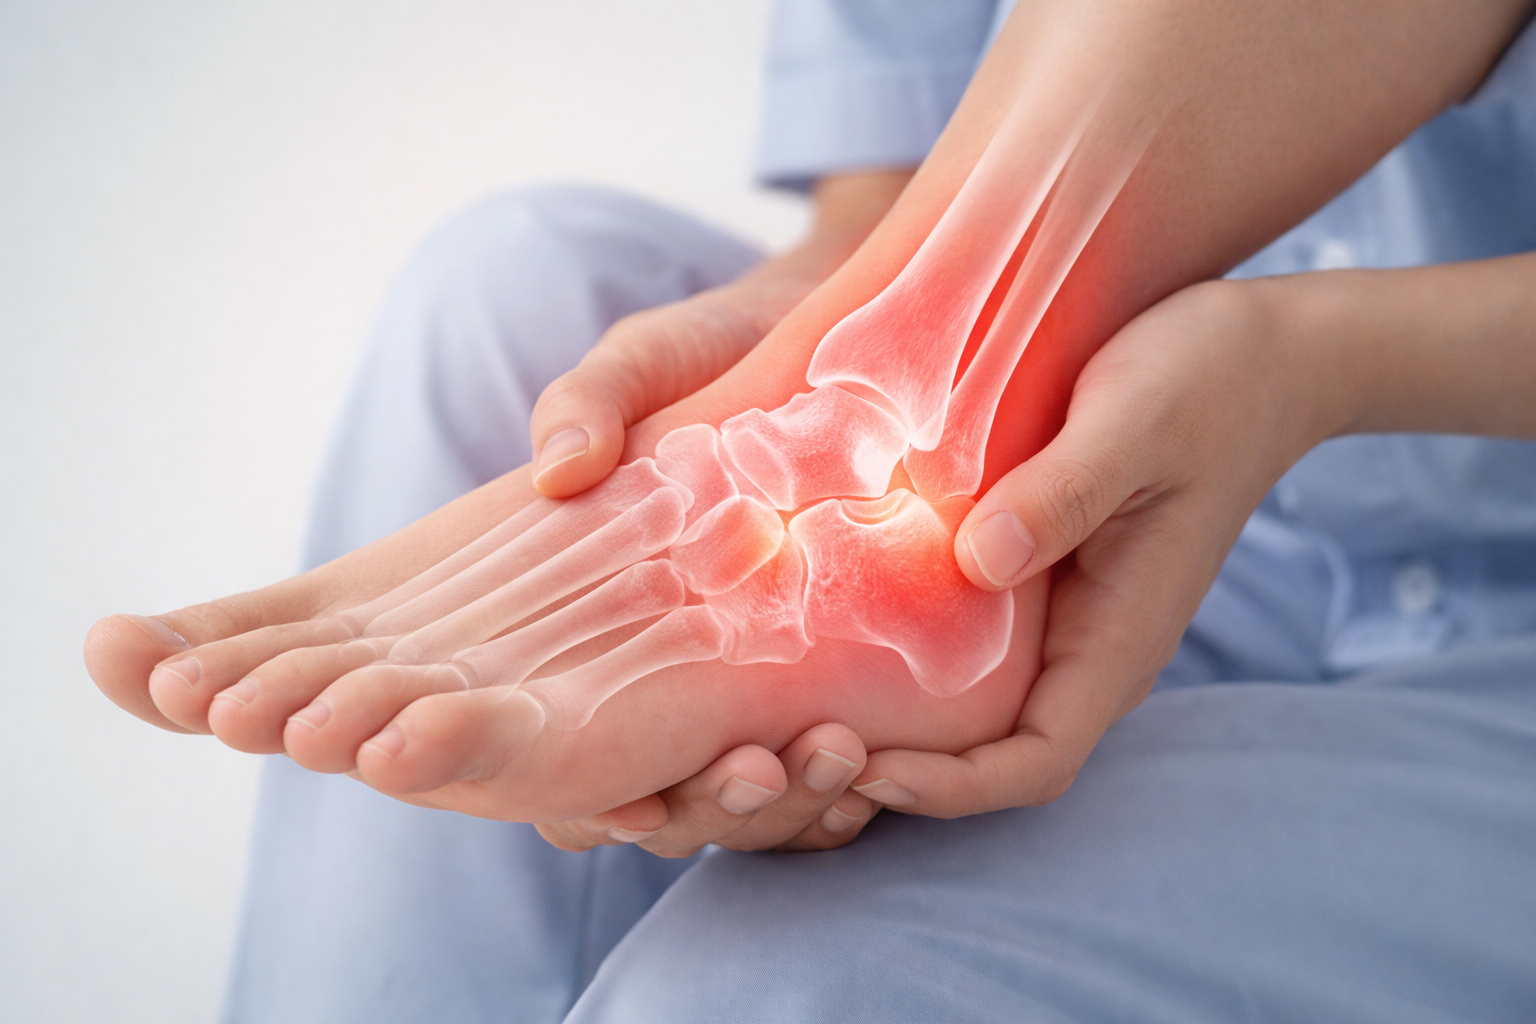

뼈, 관절 외에도 근육, 인대, 힘줄, 신경 관련 통증이나 이상 증상도 진료하나요?

네, 샘플 정형외과는 근골격계 전체를 다루는 전문 분야로, 퇴행성 질환부터 외상, 만성 통증에 이르기까지 포괄적인 진단과 맞춤형 비수술/수술 치료 계획을 제공합니다.